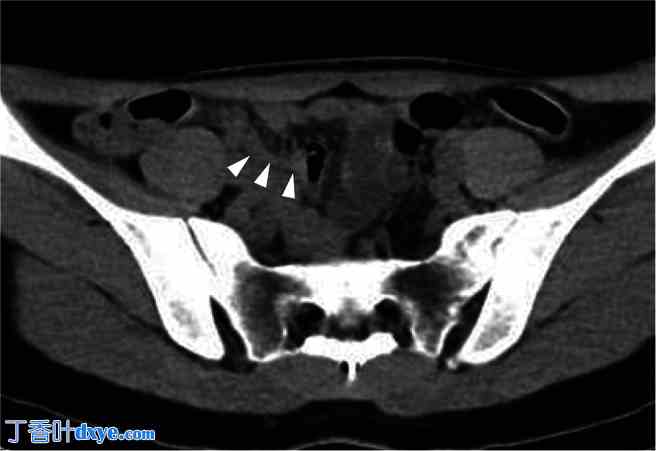

图 5

CT扫描中的阑尾扩大。

腹腔镜手术后对术前 CT 扫描进行重新评估,发现阑尾增大(箭头)。